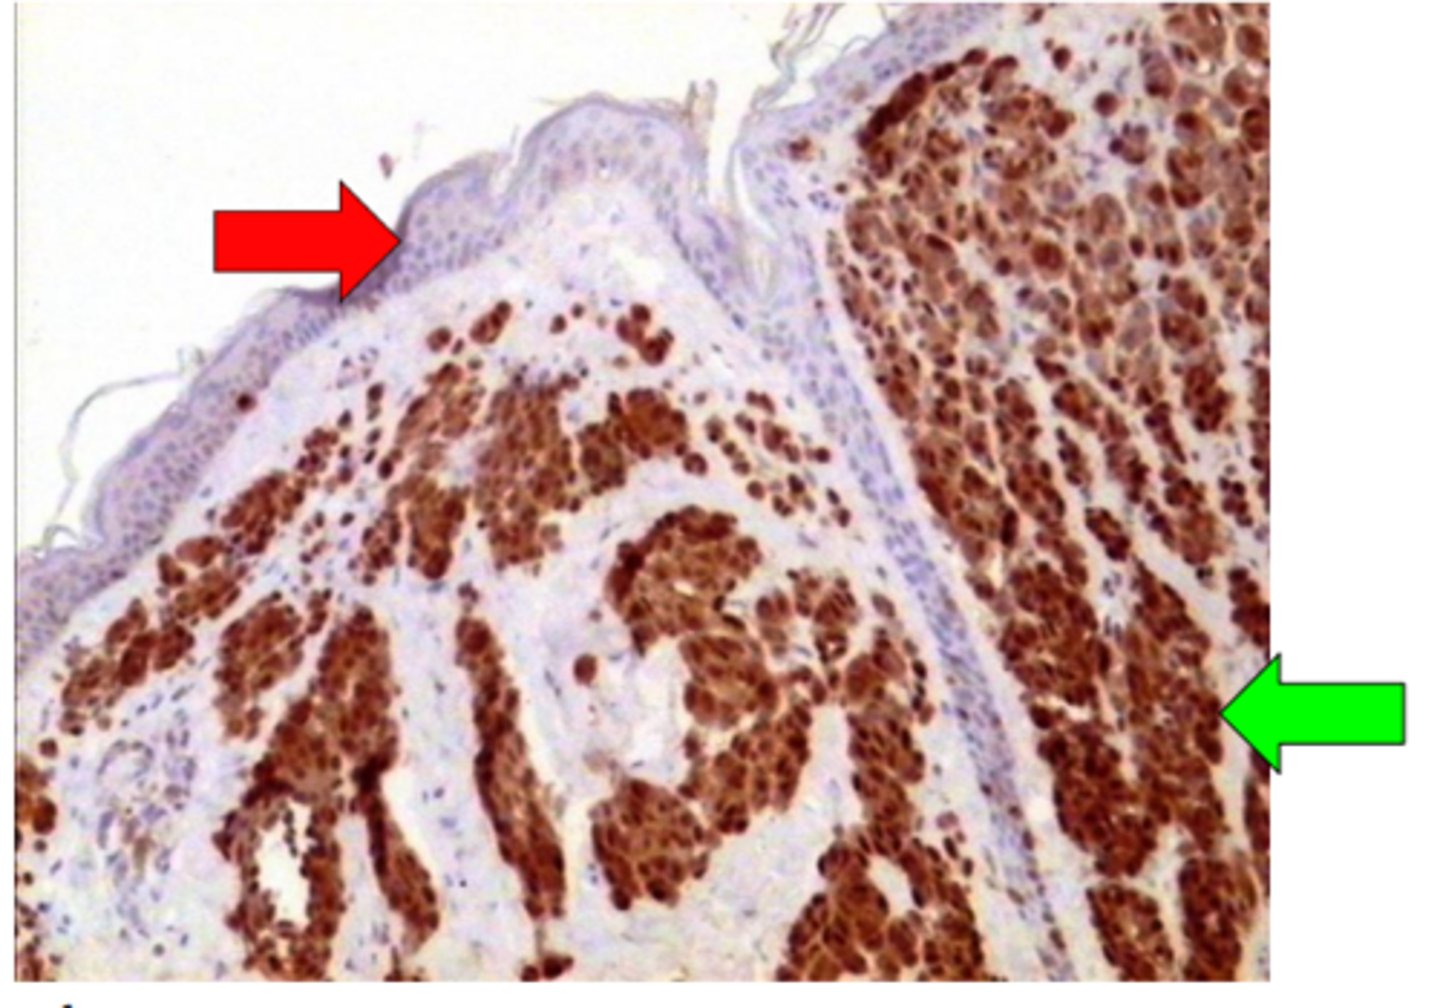

Intradermāls naevus. Anti - S100